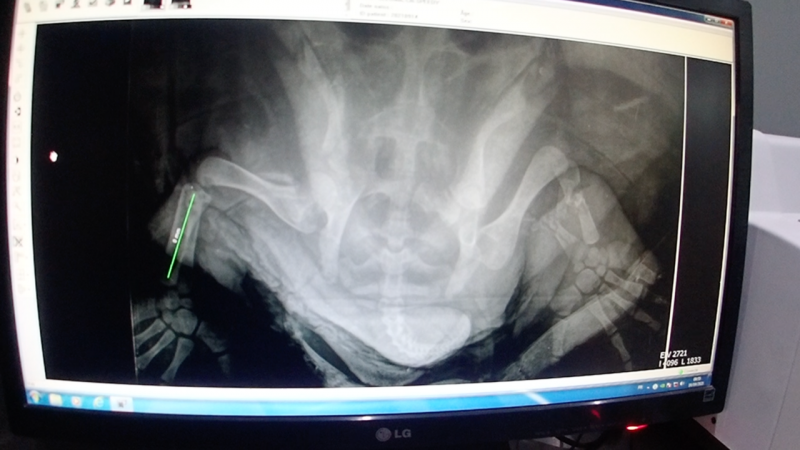

Speedy avait été victime en novembre 2021 d’un choc violent. Les blessures observées sont caractéristiques des lésions provoquées par des Foils.